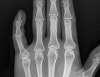

X-ray : 근위 지골 골절(proximal phalanx fracture)